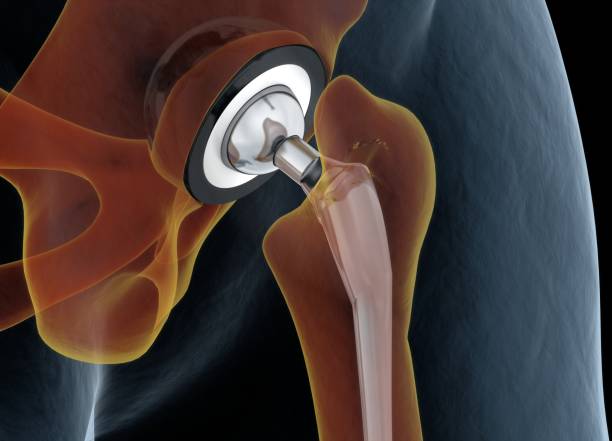

Replacement of a damaged joint with an artificial one made of metal, ceramic, or plastic.

How is Joint Replacement Surgery Performed?

The damaged joint is removed and replaced with a prosthesis fixed securely to allow smooth movement.